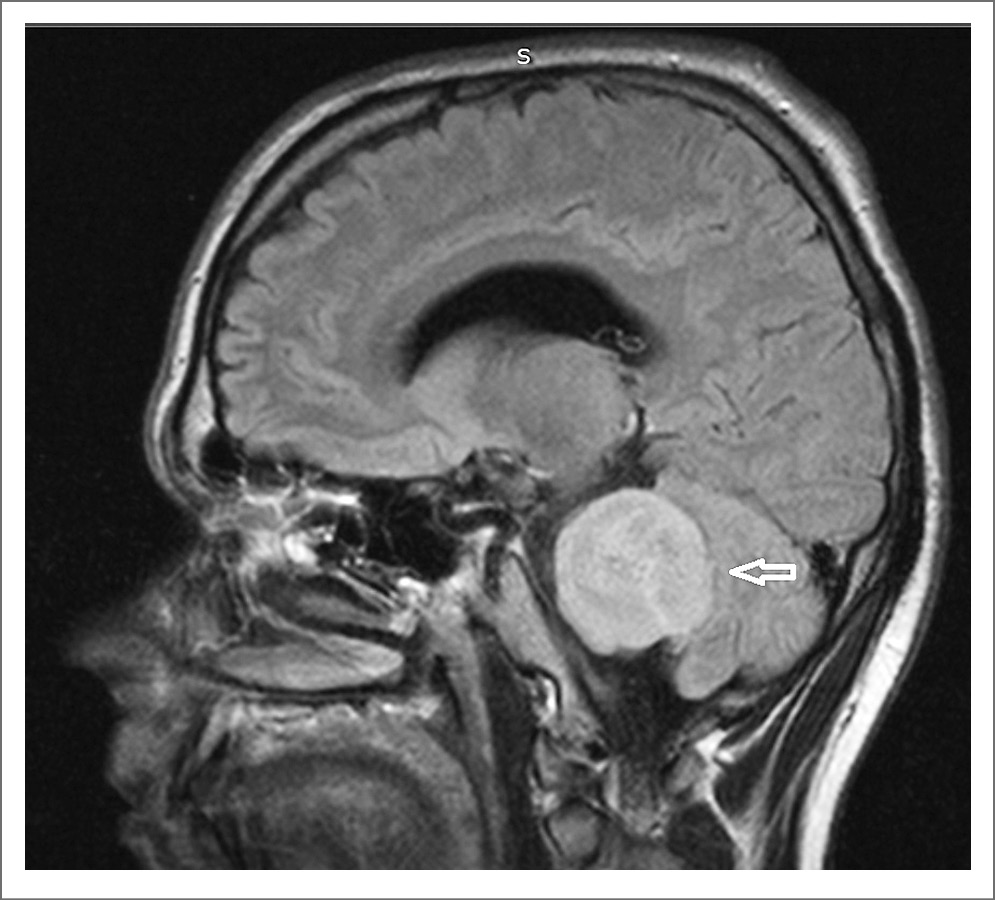

Пациент явился на повторный прием 15.12.21 с результатами магнитно-резонансной томографии (МРТ) головного мозга (рис. 1, 2). Заключение: «МР-картина объемного образования левой гемисферы мозжечка. Учитывая наличие сифилиса (со слов пациента) в анамнезе, МР-картина может соответствовать гуммозной форме нейросифилиса. МР-картина дислокационного синдрома продолговатого мозга, начальные признаки окклюзионной гидроцефалии. Единичные гиперинтенсивные очаги в белом веществе головного мозга, вероятно, как проявление микроангиопатии».

Рис. 2. Результаты МРТ головного мозга пациента И. (стрелкой отмечено объемное образование левой гемисферы мозжечка).

Пациент повторно проконсультирован неврологом. Диагноз: «нейросифилис с симптомами. Гуммозная? форма. Дислокационный синдром. Астенический синдром. Вестибуло-атактический синдром». С учетом изменений, обнаруженных на МРТ головного мозга от 11.12.21, пациенту необходима экстренная госпитализация в нейрохирургический стационар. От предложенной госпитализации по каналу скорой медицинской помощи пациент отказался, оформлен отказ от госпитализации в присутствии лечащего врача и заведующего МГРЦДС. Дано направление на госпитализацию. Пациенту разъяснены результаты дообследования и возможные осложнения.